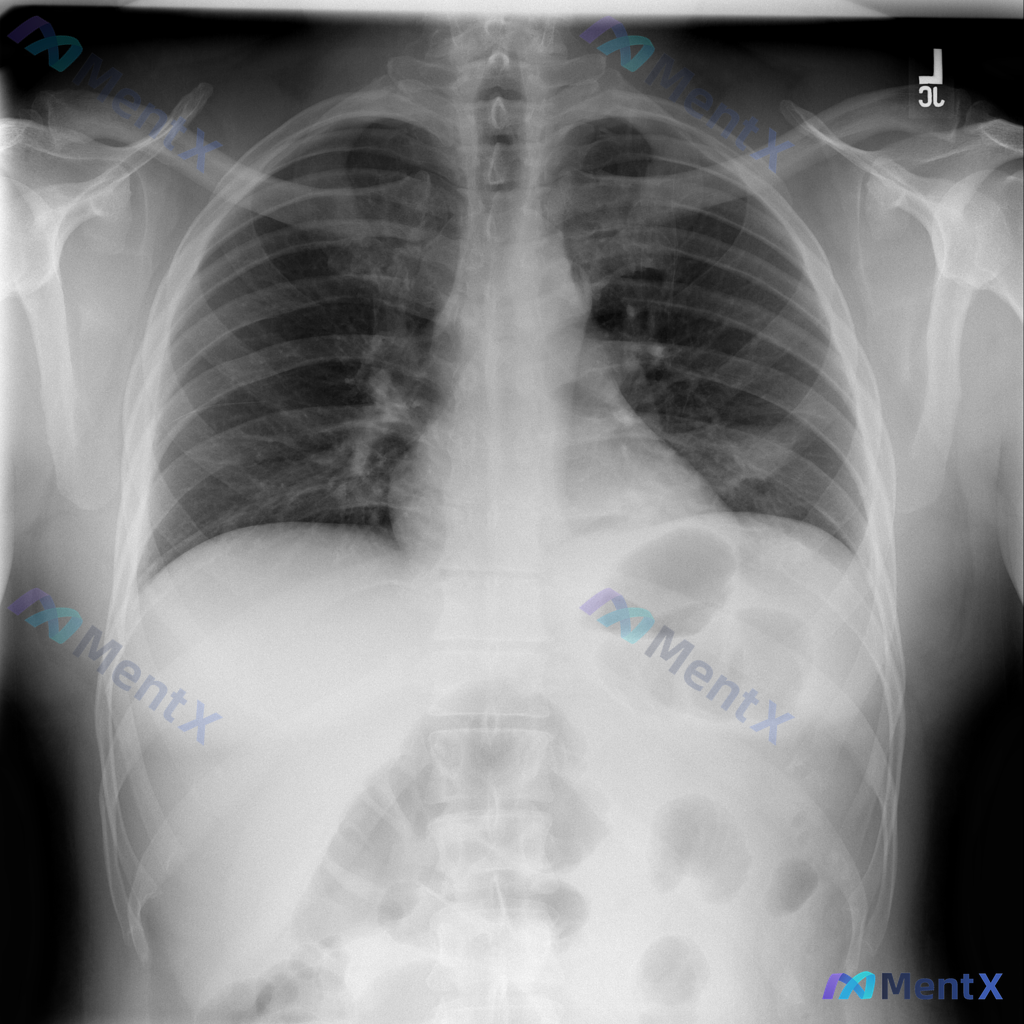

整理到一张胸部正位X光片的读片资料,先不说结论,大家看看这几个关键点: - 投照质量:曝光适中,体位居中,吸气充分,肩胛骨避开肺野 - 肺野:透亮度对称,无实变、肿块、结节,肺纹理走行尚可 - 肺门、纵隔:无增大,气管居中 - 心影:大小形态正常,心胸比<0.5 - 膈肌、肋膈角:位置正常,肋膈角尖...

整理了一份胸部正位X光片的病例资料,先把影像核心表现放出来,大家第一眼思路会怎么分? 核心影像表现 - 体位与质量:PA位,吸气尚可,无明显旋转,曝光适中 - 肺野:双侧肺野弥漫性纹理增粗、紊乱,双肺门区及中下野可见较多细小结节状、网格状及条索状阴影,以双侧中下肺野为著;双上肺尖段可见少许纤维条索影...